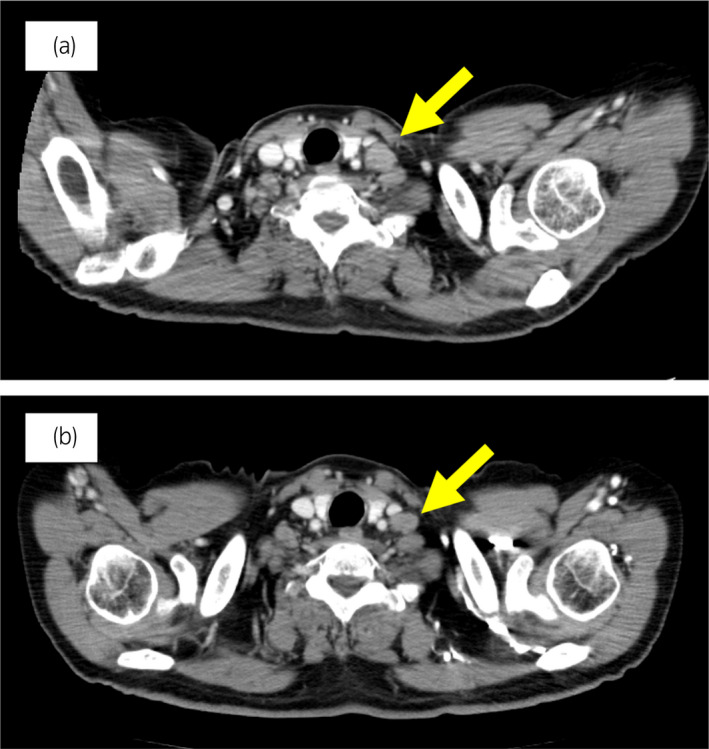

70 岁男性被诊断为转移性 PC,cT3bN1M1b,Gleason 评分(GS)为 4 + 5 = 9,前列腺特异性抗原(PSA)水平为 40.8ng/ml,3 年前伴有胸椎转移。 对前列腺进行联合雄激素阻断 (CAB) 治疗和质子放射治疗 (78.0Gy/39fr)。 PSA 水平降至 <0.01ng/ml,CAB 在 2.5 年后停止。 停止 CAB 五个月后,他出现背痛,PSA <0.01 ng/ml。 计算机断层扫描 (CT) 扫描检测到多处肝、骨和淋巴结转移,神经元特异性烯醇化酶 (NSE) 水平高达 171ng/ml(图 1a)。 骨转移活检显示神经内分泌前列腺癌 (NEPC) 的诊断(图 2),患者被转诊至佳学基因合作医院。 内分泌肿瘤精准治疗医生用顺铂、依托泊苷和亮丙瑞林治疗。 第三个疗程后,转移部位明显缩小(图 1b)。 顺铂和依托泊苷治疗 1 年,但患者因神经病变要求停药。 他开始服用恩杂鲁胺。 治疗 3 个月后,患者出现背痛和左锁骨下淋巴结肿大(图 3a)。 肝转移保持不变,顺铂治疗后缩小。 通过肿瘤精准用药850基因检测证实了 BRCA2 突变。根据基因检测结果,主治肿瘤科医生给予了奥拉帕尼。 三个月后,背痛好转,淋巴结转移缩小,确定为部分缓解(PR)(图3b)。 肝转移灶保持不变。

图 3:案例 1. 开始使用奥拉帕尼之前和之后 3个月的锁骨下淋巴结转移的 CT 图像。 (a) 治疗前和 (b) 奥拉帕尼治疗后 3 个月。 黄色箭头显示转移淋巴结。